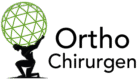

Vergleich zwischen gesundem Kniegelenk und fortgeschrittener Kniearthrose

Eine Kniegelenksprothese ist ein künstlicher Ersatz für das natürliche Kniegelenk, bei dem die abgenutzten Gelenkflächen durch speziell angefertigte Implantate ersetzt werden. Diese bestehen in der Regel aus einer Metalllegierung (meist Chrom-Kobalt-Molybdän) für die Oberschenkel- und Schienbeinkomponente sowie einem Kunststoffteil (Polyethylen) als Gleitfläche zwischen den Metallkomponenten.

Die medizinische Notwendigkeit für eine Knieprothese ergibt sich typischerweise bei fortgeschrittener Kniearthrose (Gonarthrose), wenn der Gelenkknorpel so stark abgenutzt ist, dass Knochen auf Knochen reibt. Dies führt zu chronischen Schmerzen, eingeschränkter Beweglichkeit und einer deutlichen Beeinträchtigung der Lebensqualität. Auch nach schweren Knieverletzungen, bei rheumatischen Erkrankungen oder bei Knochenerkrankungen wie der aseptischen Knochennekrose kann eine Knieprothese notwendig werden.